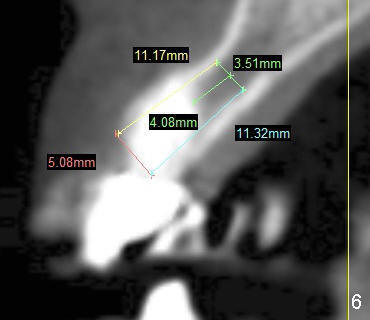

CT taken before the fracture shows that the mesiodistal and buccolingual widths of the tooth at the crest in axial section are 4.61 mm and 5.98 mm, respectively (Fig.2).